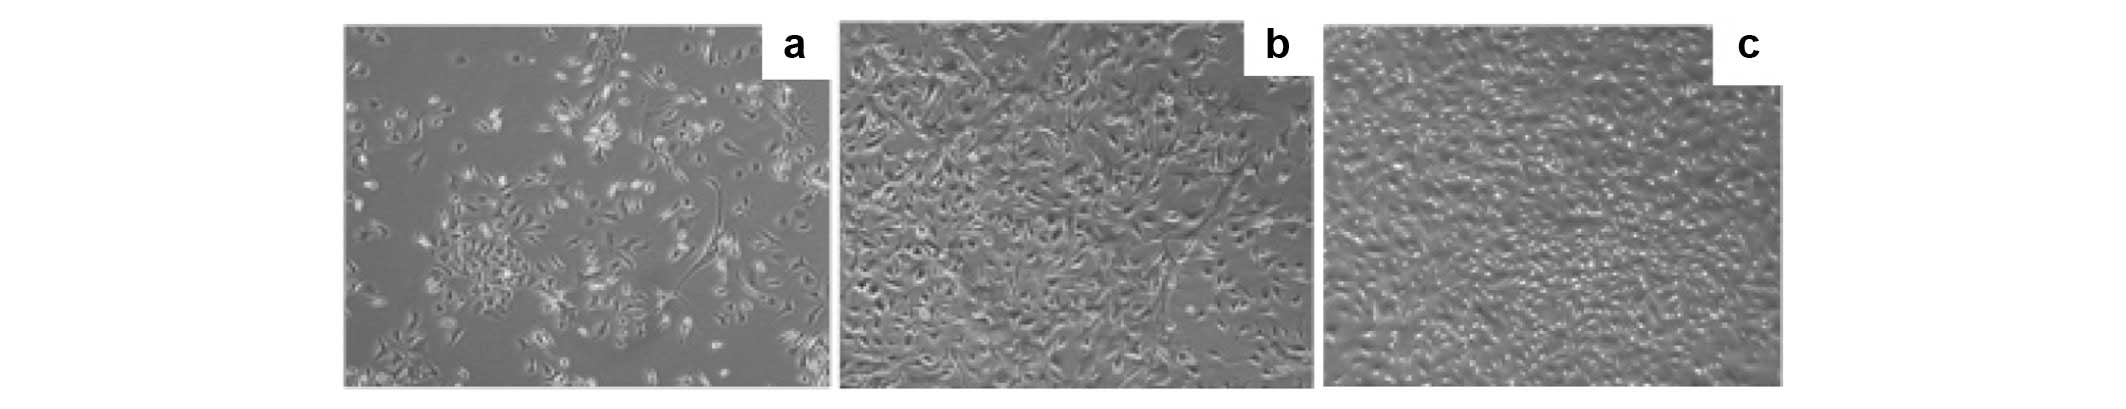

Prostate cancer (PCa) is the most common type of cancer worldwide. Mesenchymal stem cells (MSCs) can also be utilized as ‘tumor stromal cells’, which are associated with invasive and metastatic malignant tumor cells. Our study aimed to investigate MSCs in prostate tumors and normal MSCs and evaluate their differential characteristics. Normal MSCs (BMMSCs) were isolated from the femur and tibia of normal mice; prostate tumor MSCs (PCa-MSCs) were obtained from prostate tumors implanted in mice. These two types of MSCs were induced to differentiate into adipocytes, bone cells and chondrocytes. Growth curves were used to analyze the growth ability of PCa-MSCs and BMMSCs. Tritium-labeled thymidine (3H-TdR) was used to evaluate cell proliferation of RM-1 stimulated by MSCs. The time taken for PCa-MSCs to reach 90% confluence was markedly shorter than that of BMMSCs (8-10 vs. 12-14 days). The differentiation ability of PCa-MSCs was similar to that described in previous reports. The growth ability of PCa-MSCs was significantly higher than that of BMMSCs. The proliferative activity of PCa-MSCs was also higher than that of BMMSCs. Our data showed that PCa-MSCs exhibit identical characteristics when compared with those of MSCs. Additionally, their proliferative activity and growth ability were significantly higher when compared with these values in BMMSCs, which appear to have an intrinsic, cell-specific capacity to localize to PCa. The possible role of PCa-MSCs in the process of PCa development requires further clarification.

Figure 3